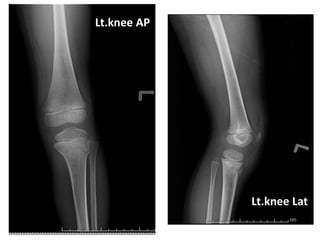

Radiographic findings

Lt.knee AP

Lt.knee Lat